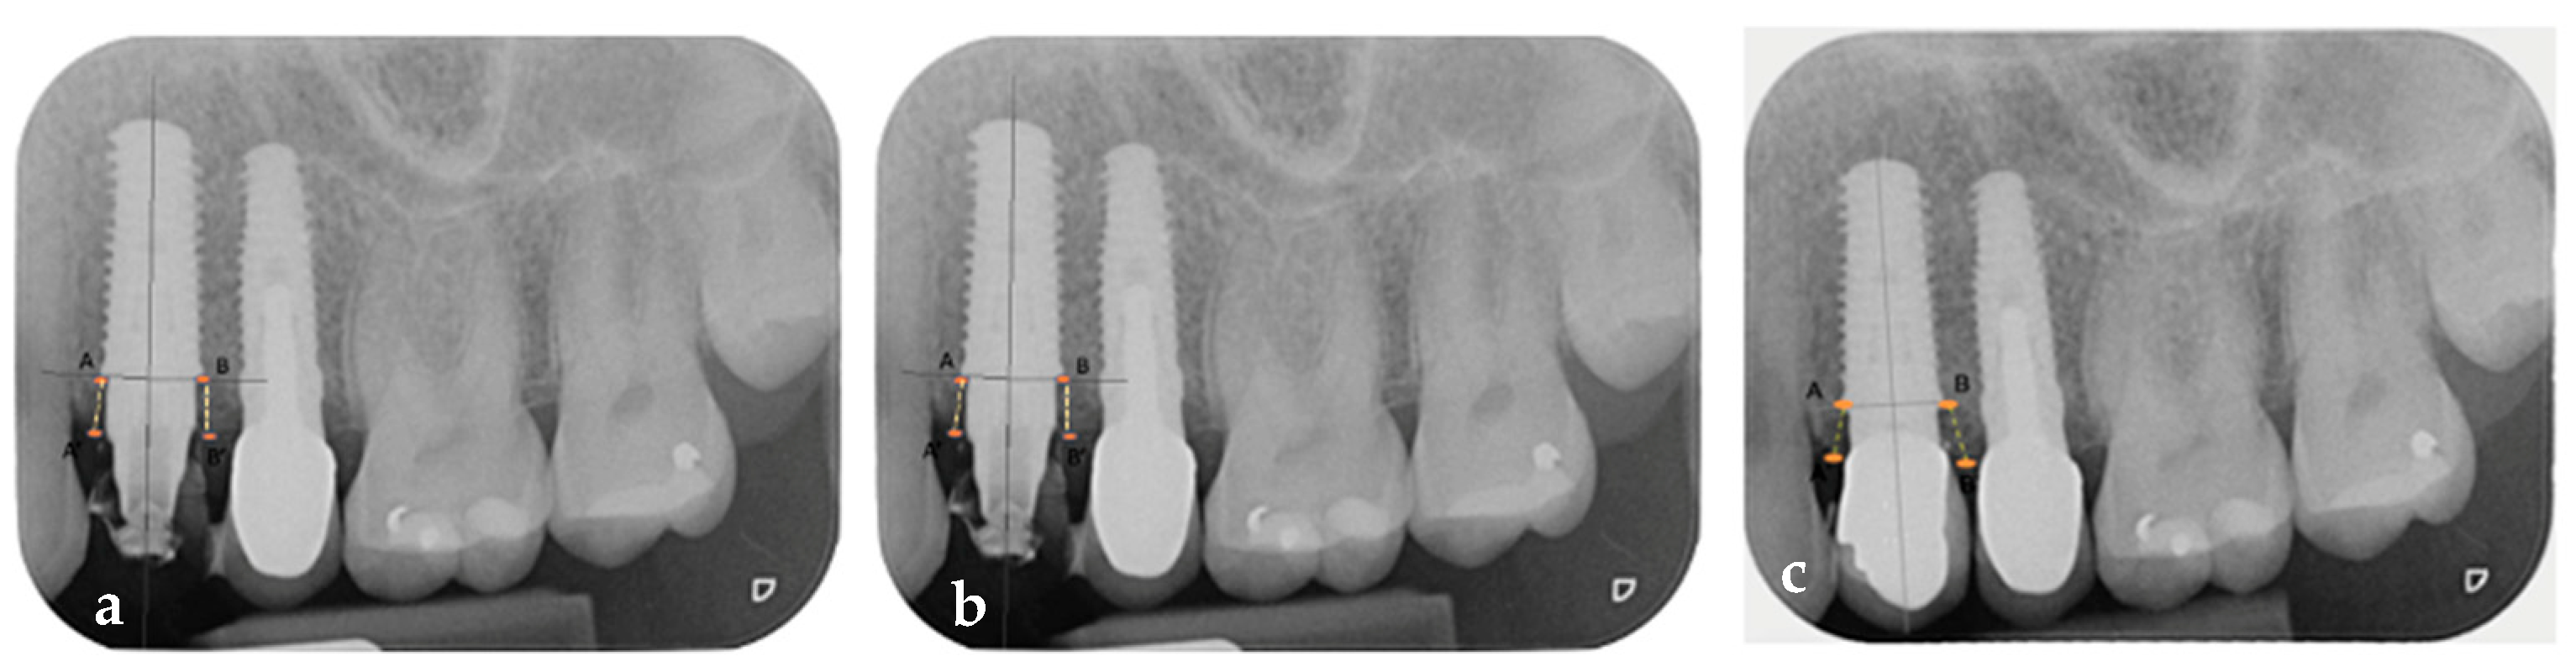

2.2. Measurements

- Keratinized mucosa width (KMW) values of 4 mm before surgery, 4 mm at 6 months, and 5 mm at 1 year after implant, customized abutment, coping, and restoration placement.